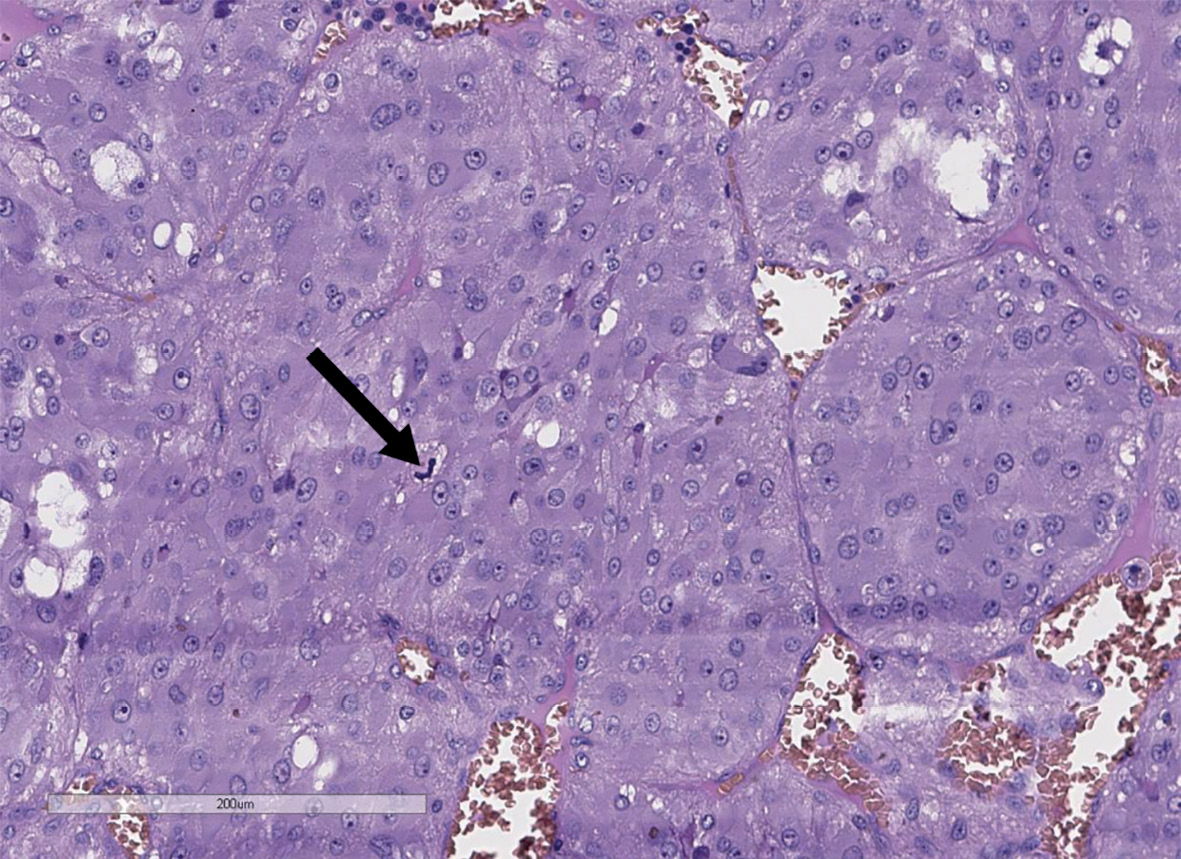

Удаленное новообразование левого надпочечника было представлено единым узлом буро-коричневого цвета диаметром до 3 см (рис. 4). При гистологическом исследовании определялась опухоль солидного и гнездного строения из хромаффинных клеток с оксифильной цитоплазмой. На 10 полей зрения выявлен 1 митоз (рис. 5). При проведении иммуногистохимического исследования в опухоли выявлена диффузная экспрессия хромогранина А, синаптофизина, АКТГ (рис. 6). Для оценки рецепторного статуса опухоли выполнена оценка экспрессии рецепторов соматостатина 2А типа (SSTR 2А) — 2 балла. Индекс пролиферации (Ki67) менее 5%. Учитывая результаты гистологического и иммуногистохимического исследований, поставлен диагноз феохромоцитомы, секретирующей АКТГ.

Рисунок 5. Гистологическое строение феохромоцитомы левого надпочечника

(стрелкой показан митоз), гематоксилин-эозин, 200х.